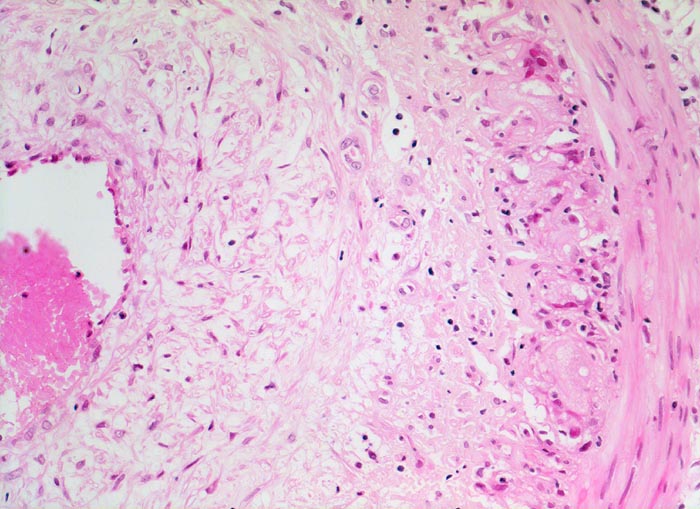

Histologisch diagnostisch ist der Nachweis von monohistiozytären Entzündungsinfiltraten entlang der Lamina elastica interna und deren Fragmentierung bzw. Zerstörung über längere Strecken (> 242). In frischen Läsionen findet sich die Entzündung unter Umständen ausschliesslich im Bereich der Vasa vasorum der Adventitia und der Media. In nur 50% der Fälle sind mehrkernige Riesenzellen (> 237) vorhanden. Seltenere Befunde sind eine Entzündung der Vasa vasorum, Verkalkungen der Lamina elastica, Intimaverdickungen und fibrinoide Gefässwandnekrosen. In Abwesenheit einer Entzündung lässt sich eine abgeheilte Arteritis temporalis nicht von atherosklerotischen oder unspezifischen altersbedingten Veränderungen der Arterie unterscheiden.

• Arteriensegment mit dichten, zirkulären lymphohistioplasmazellulären Entzündungsinfiltraten mit Beteiligung neutrophiler Granulozyten in allen Wandschichten (Adventitia, Media und Intima).

• Histiozyten und mehrkernige Riesenzellen finden sich bevorzugt entlang der Lamina elastica interna. Die Riesenzellen enthalten teilweise phagozytierte Fragmente der Lamina elastica interna.

• Fragmentierung, Abblassung und herdförmig Zerstörung der Lamina elastica interna über längere Strecken (EvG Färbung).

• Ausgeprägte Intimafibrose mit mit dichten Infiltraten zerfallender neutrophiler Granulozyten.

• Das Gefässlumen partiell obliterierender frischer Gerinnungsthrombus. Das sollte der Kliniker dem Pathologen mitteilen: